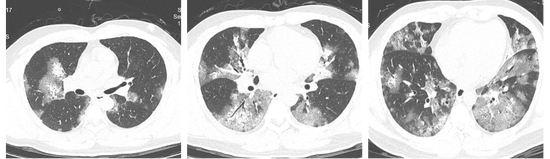

结果显示,刘先生感染了甲型流感,但他的胸部CT让接诊医生意识到不仅仅是普通的流感这么简单。

刘先生的两肺都有非常严重的磨玻璃样渗出,也就是平时所说的“白肺”。

结合病史,接诊医生考虑刘先生得了重症流感,在汇报吕群后,赶紧把刘先生收入院治疗。

吕群分析,以往高致病性禽流感、新冠病毒感染等病毒性肺炎,在病情严重时都有可能引发“白肺”现象。但是像刘先生这样因甲流感染而导致的重症流感病例,并进展到出现显著肺部病变乃至“白肺”的程度,相对而言还是较为少见的。

刘先生的氧饱和度下降至85%,应给予吸氧辅以抗病毒、激素冲击、免疫球蛋白等治疗。

在医护人员的努力下,刘先生的病情逐渐稳定,高烧逐渐消退,胸闷气急的症状也得到了缓解。再次复查胸部CT,两肺的炎性渗出都有不同程度的吸收。经过这次大病,刘先生感觉重获新生。